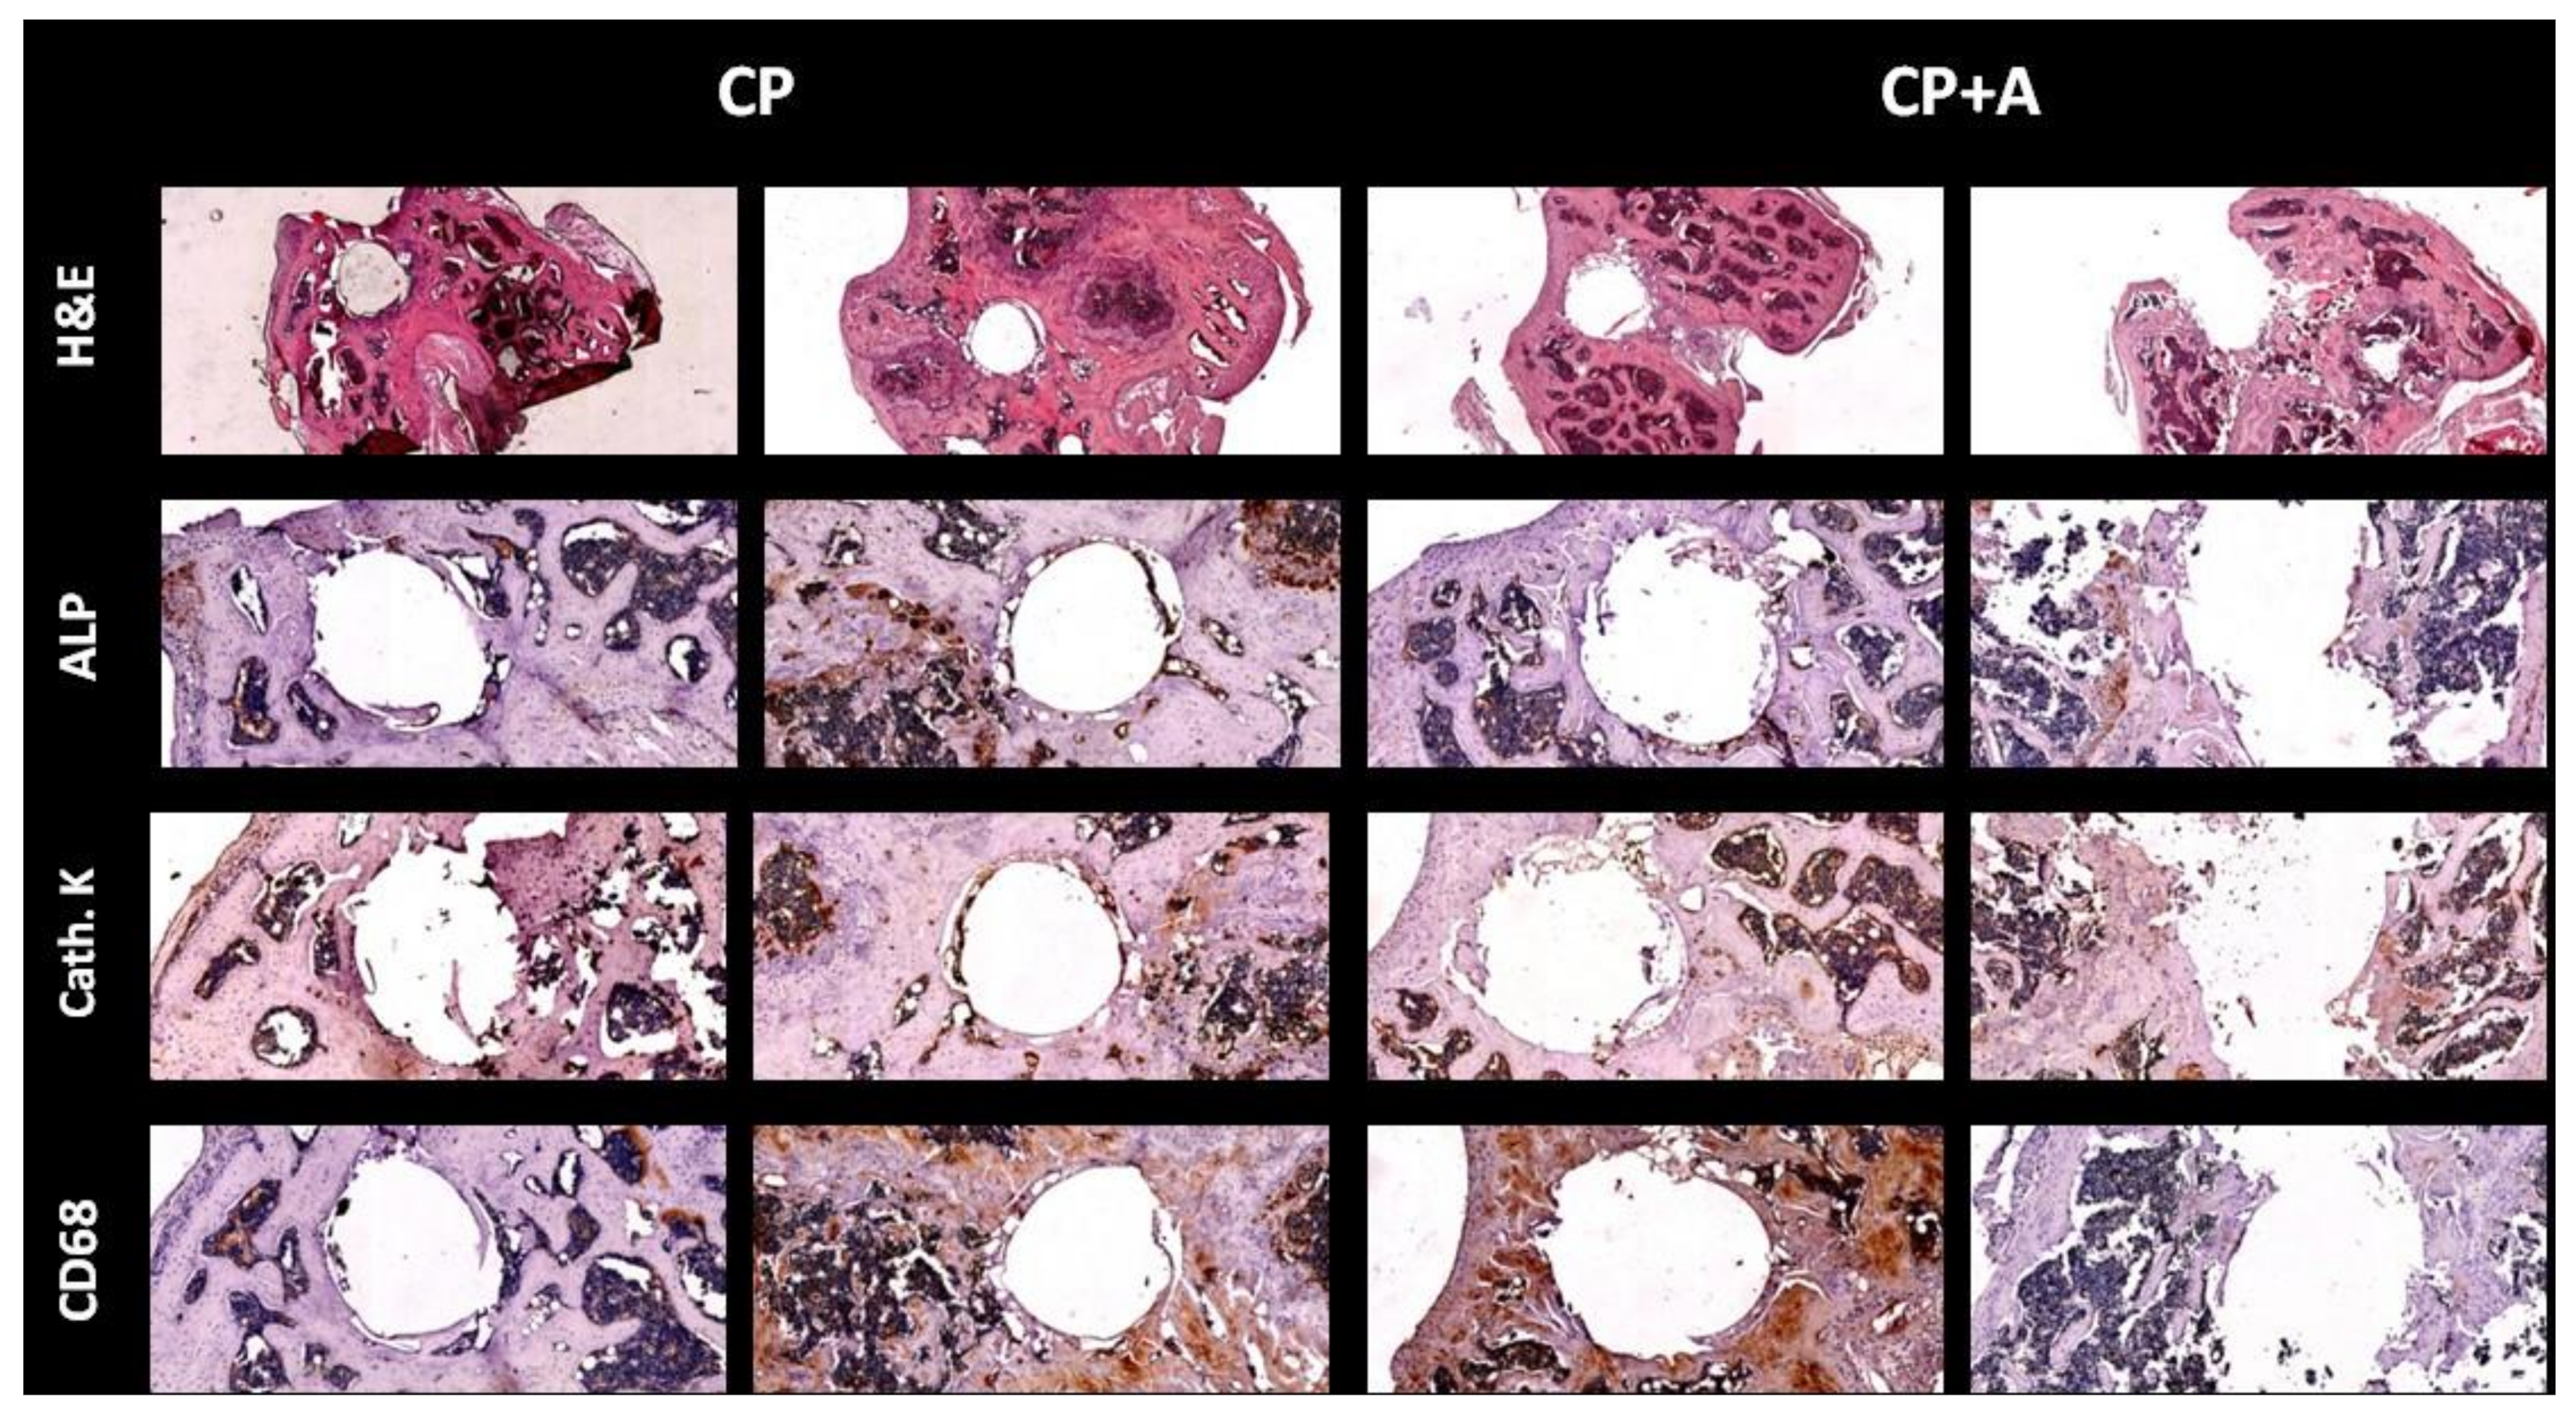

2.2. Microbiological and Pathological Results

2.3. Microcomputed Tomography and Bone Histology

- Acute osteomyelitis was defined as bone tissue evidencing moderate-to-high–intensity polymorphonuclear (PMN) inflammatory response with tissue necrosis phenomena and trapping of trabecular bone remains;

- Chronic osteomyelitis was defined as bone tissue that presents a variable inflammatory reaction, partially consisting of a PMN response, but mainly of plasma cells and lymphocytes;

- PJI was diagnosed when any type of osteomyelitis and the presence of yeast were evidenced.

4.5. Immunohistochemistry